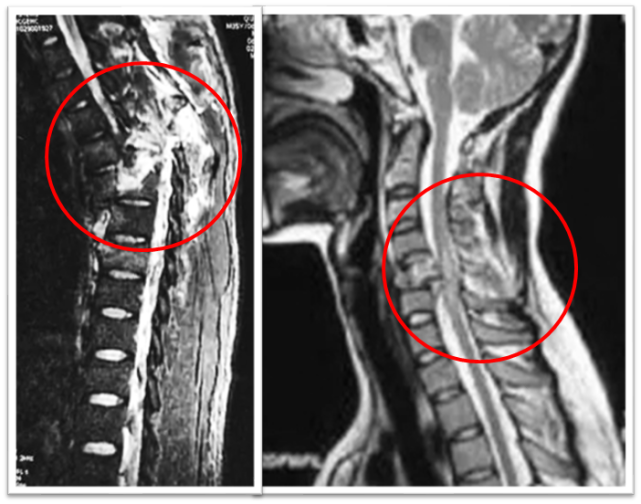

图片

正中间灰色的竖条就是脊髓,箭头指的,灰色中的白色条纹,就是脊髓损伤的表现。